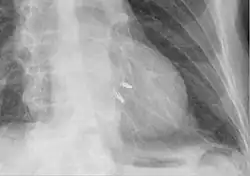

Strzałka wskazuje kierunek wstecznego przepływu krwi z lewej komory do lewego przedsionka podczas skurczu

1 – zastawka mitralna

2 – lewa komora

3 – lewy przedsionek

4 – aorta